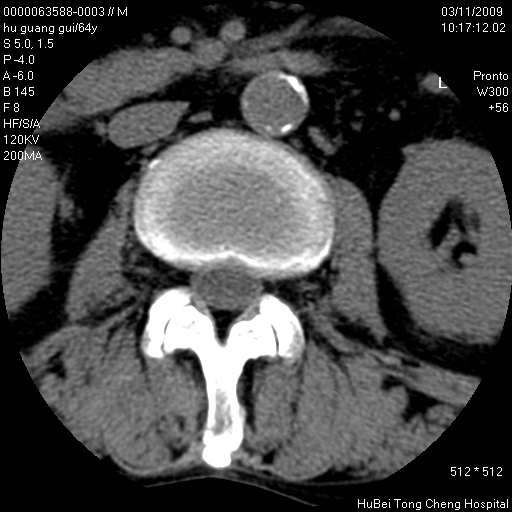

患者 男,64岁。腰痛十余天。(临床未提供其他病史)

临床诊断:腰痛原因待查(腰椎间盘突出症?)。

腰椎间盘ct轴位平扫(层厚5mm,层距4mm),图像如下:

腰椎退行性变,腰4—5椎间盘膨出。

右侧骶骨侧块骨侵蚀,骶髂关节骨性关节面破坏,并见软组织肿块,考虑骨转移瘤可能,进一步检查。